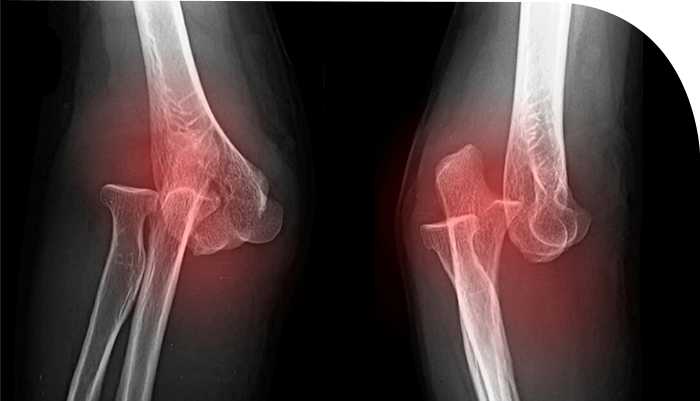

ºÒÀ¯ÇÕÀº »À°¡ ºÙÁö ¾ÊÀº »óÅ·Π°ñÀý ºÎºÐÀÇ Ä¡À¯ °úÁ¤ÀÌ º¸ÀÌÁö ¾Ê´Â »óŸ¦ ÀǹÌÇÕ´Ï´Ù.

ºÒÀ¯ÇÕÀÇ °æ¿ì °ñÀý¼±ÀÌ ¹æ»ç¼±»ó¿¡¼­ Áö¼ÓÀûÀ¸·Î º¸À̰ųª °ñÀý ³¡ ºÎÀ§¿¡ °æÈ­°¡ È®Àε˴ϴÙ.

°¡°ñÀ̶õ »À°¡ °ñÀýÀÌ µÈ ÀÌÈÄ ºÙ´Â °úÁ¤¿¡¼­ »ý±â´Â Á¤»óÀûÀÎ »À Á¶Á÷Àε¥,

ºÒÀ¯ÇÕ¿¡¼­ ¿øÀΰú Á¾·ù¿¡ µû¶ó¼­ °¡°ñ Çü¼ºÀÌ ºñ´ëÇϰųª ¾ø±âµµ ÇÕ´Ï´Ù.